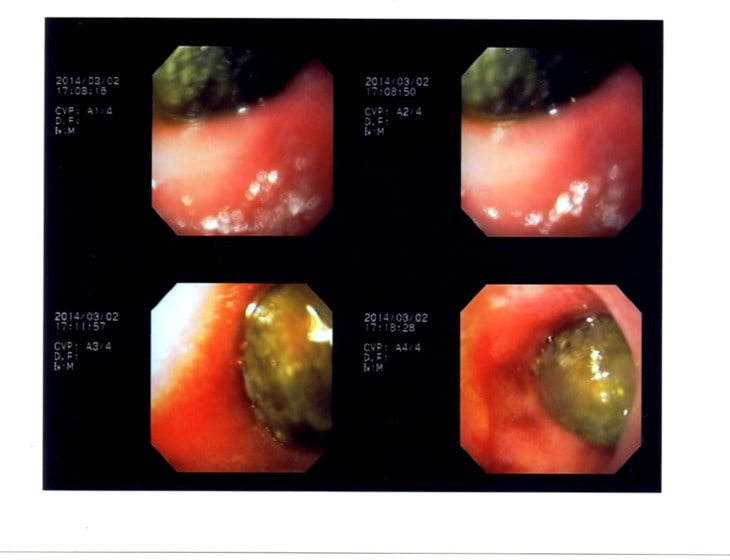

内視鏡検査結果:内視鏡下にて、バスケット鉗子を用いて摘出。

症例は、机の上に置いていたピスタチオのお菓子を誤飲していました。その後の経過は良好です。本症例は、内視鏡下にて摘出ができましたが、球状・立体などの大きな異物は、腸の途中で詰まりやすく、内視鏡下での摘出が困難な場合もあります。その際は、開腹下にて腸内の異物を摘出しなくてはなりません。動物たちは、思わぬ物を誤飲することがあります。お留守番時・就寝時は、誤飲をしやすい時間帯ですので注意しましょう。